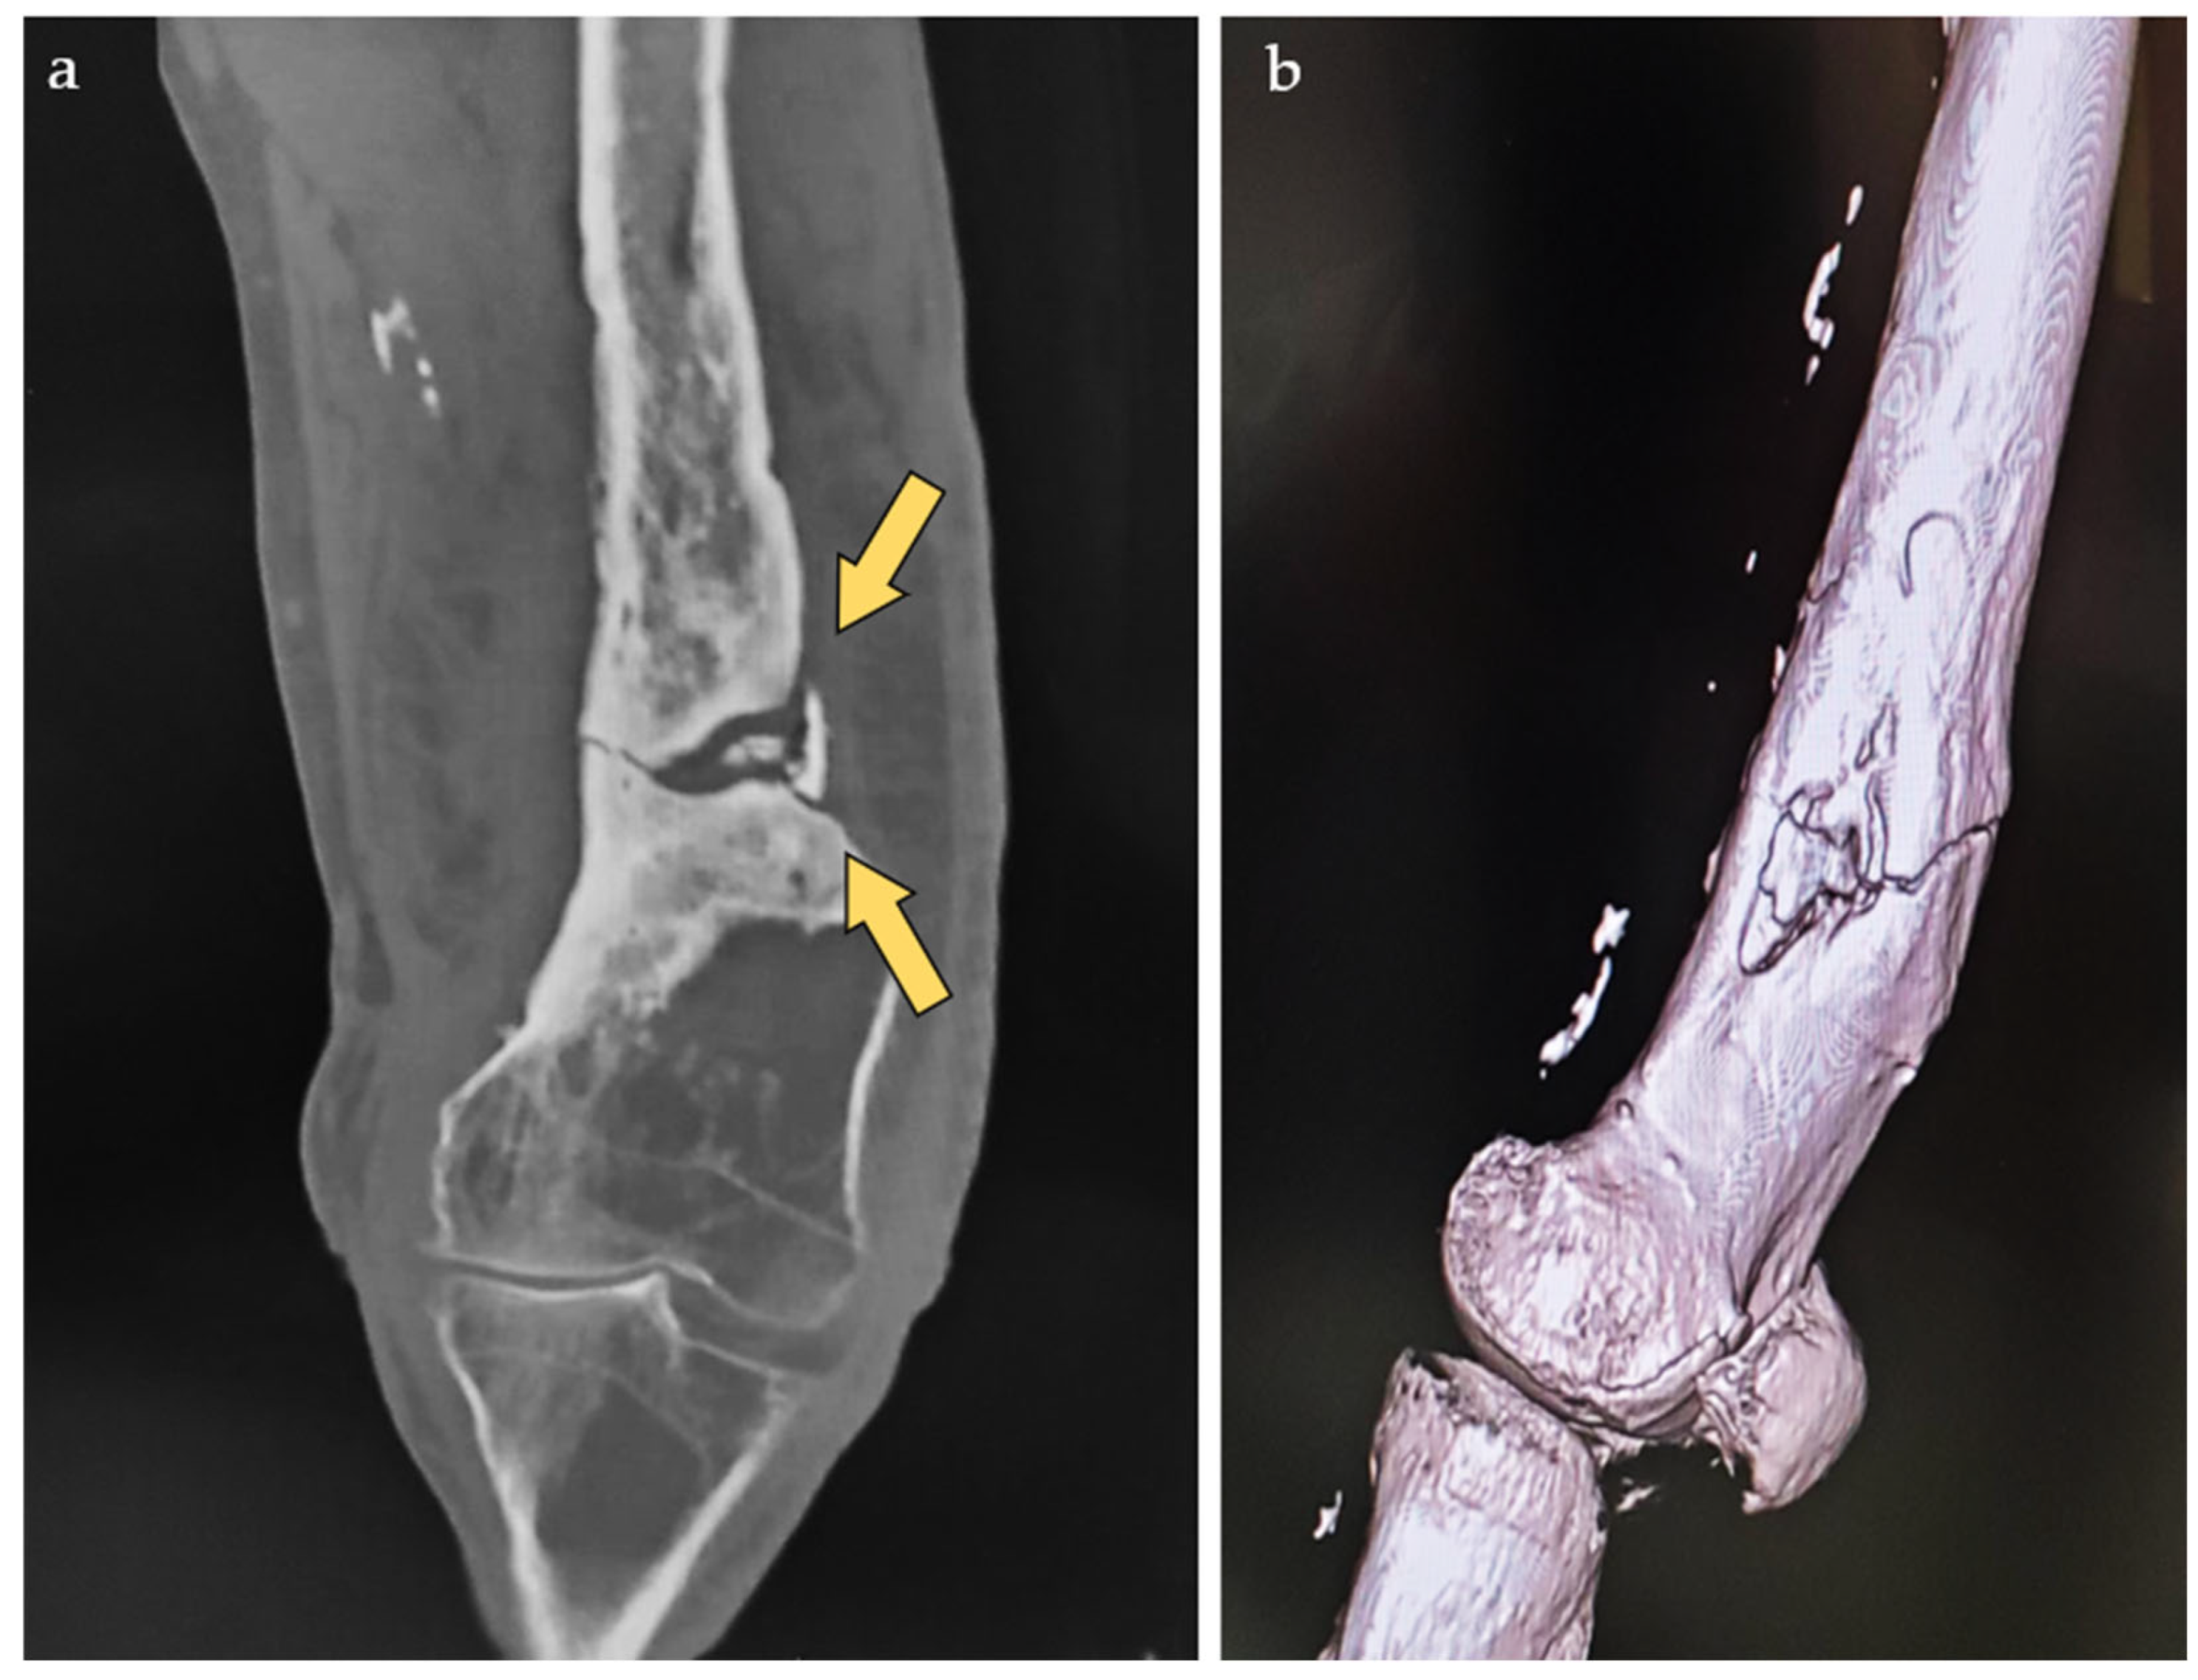

2. Case Report